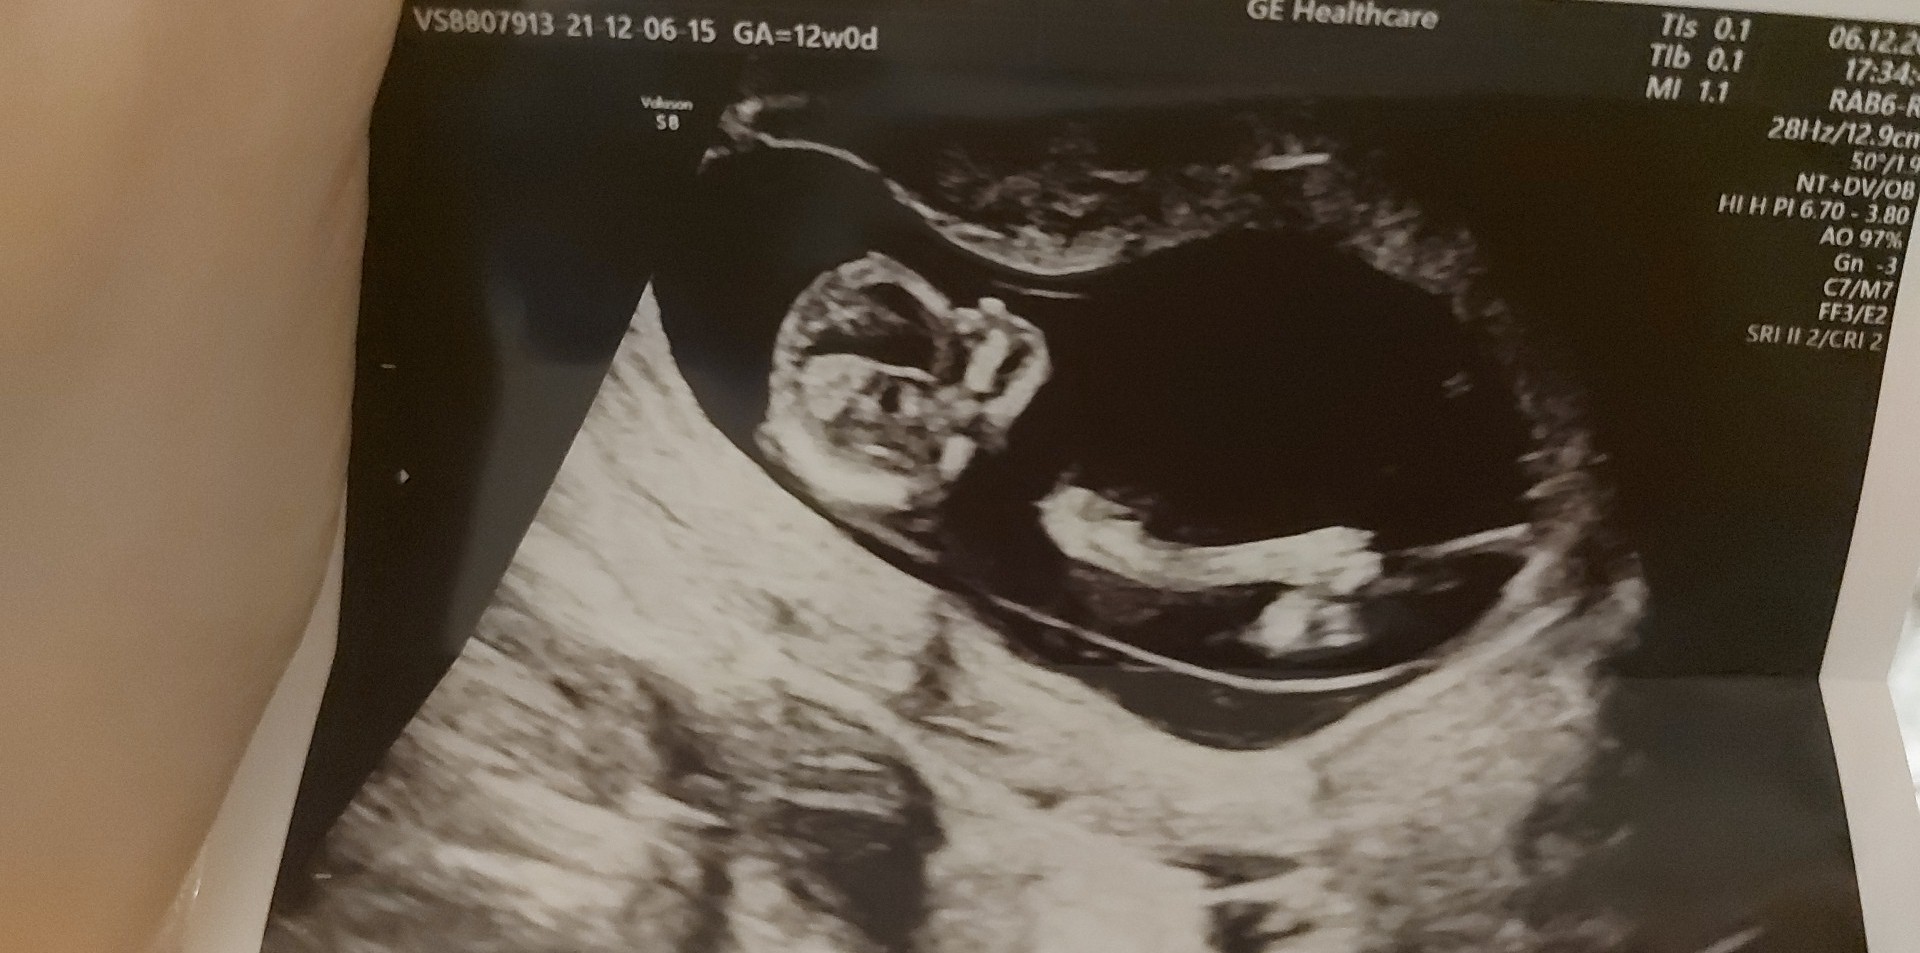

A teraz poszłam na prenatalne i lekarz był mało wylewny. Nie wiem nic. Płci jeszcze nie widać ogólnie powiwdzial że wygląda to dobrze ale mam brać acard bo przepływ krwi jest taki sobie. I nawet nie wiem jak dostanę wyniki i w ogóle. Krew na pappa pobrana. 9 idę do swojego gina i się dowiem co i jak bo serio nie wiem co mam myśleć.